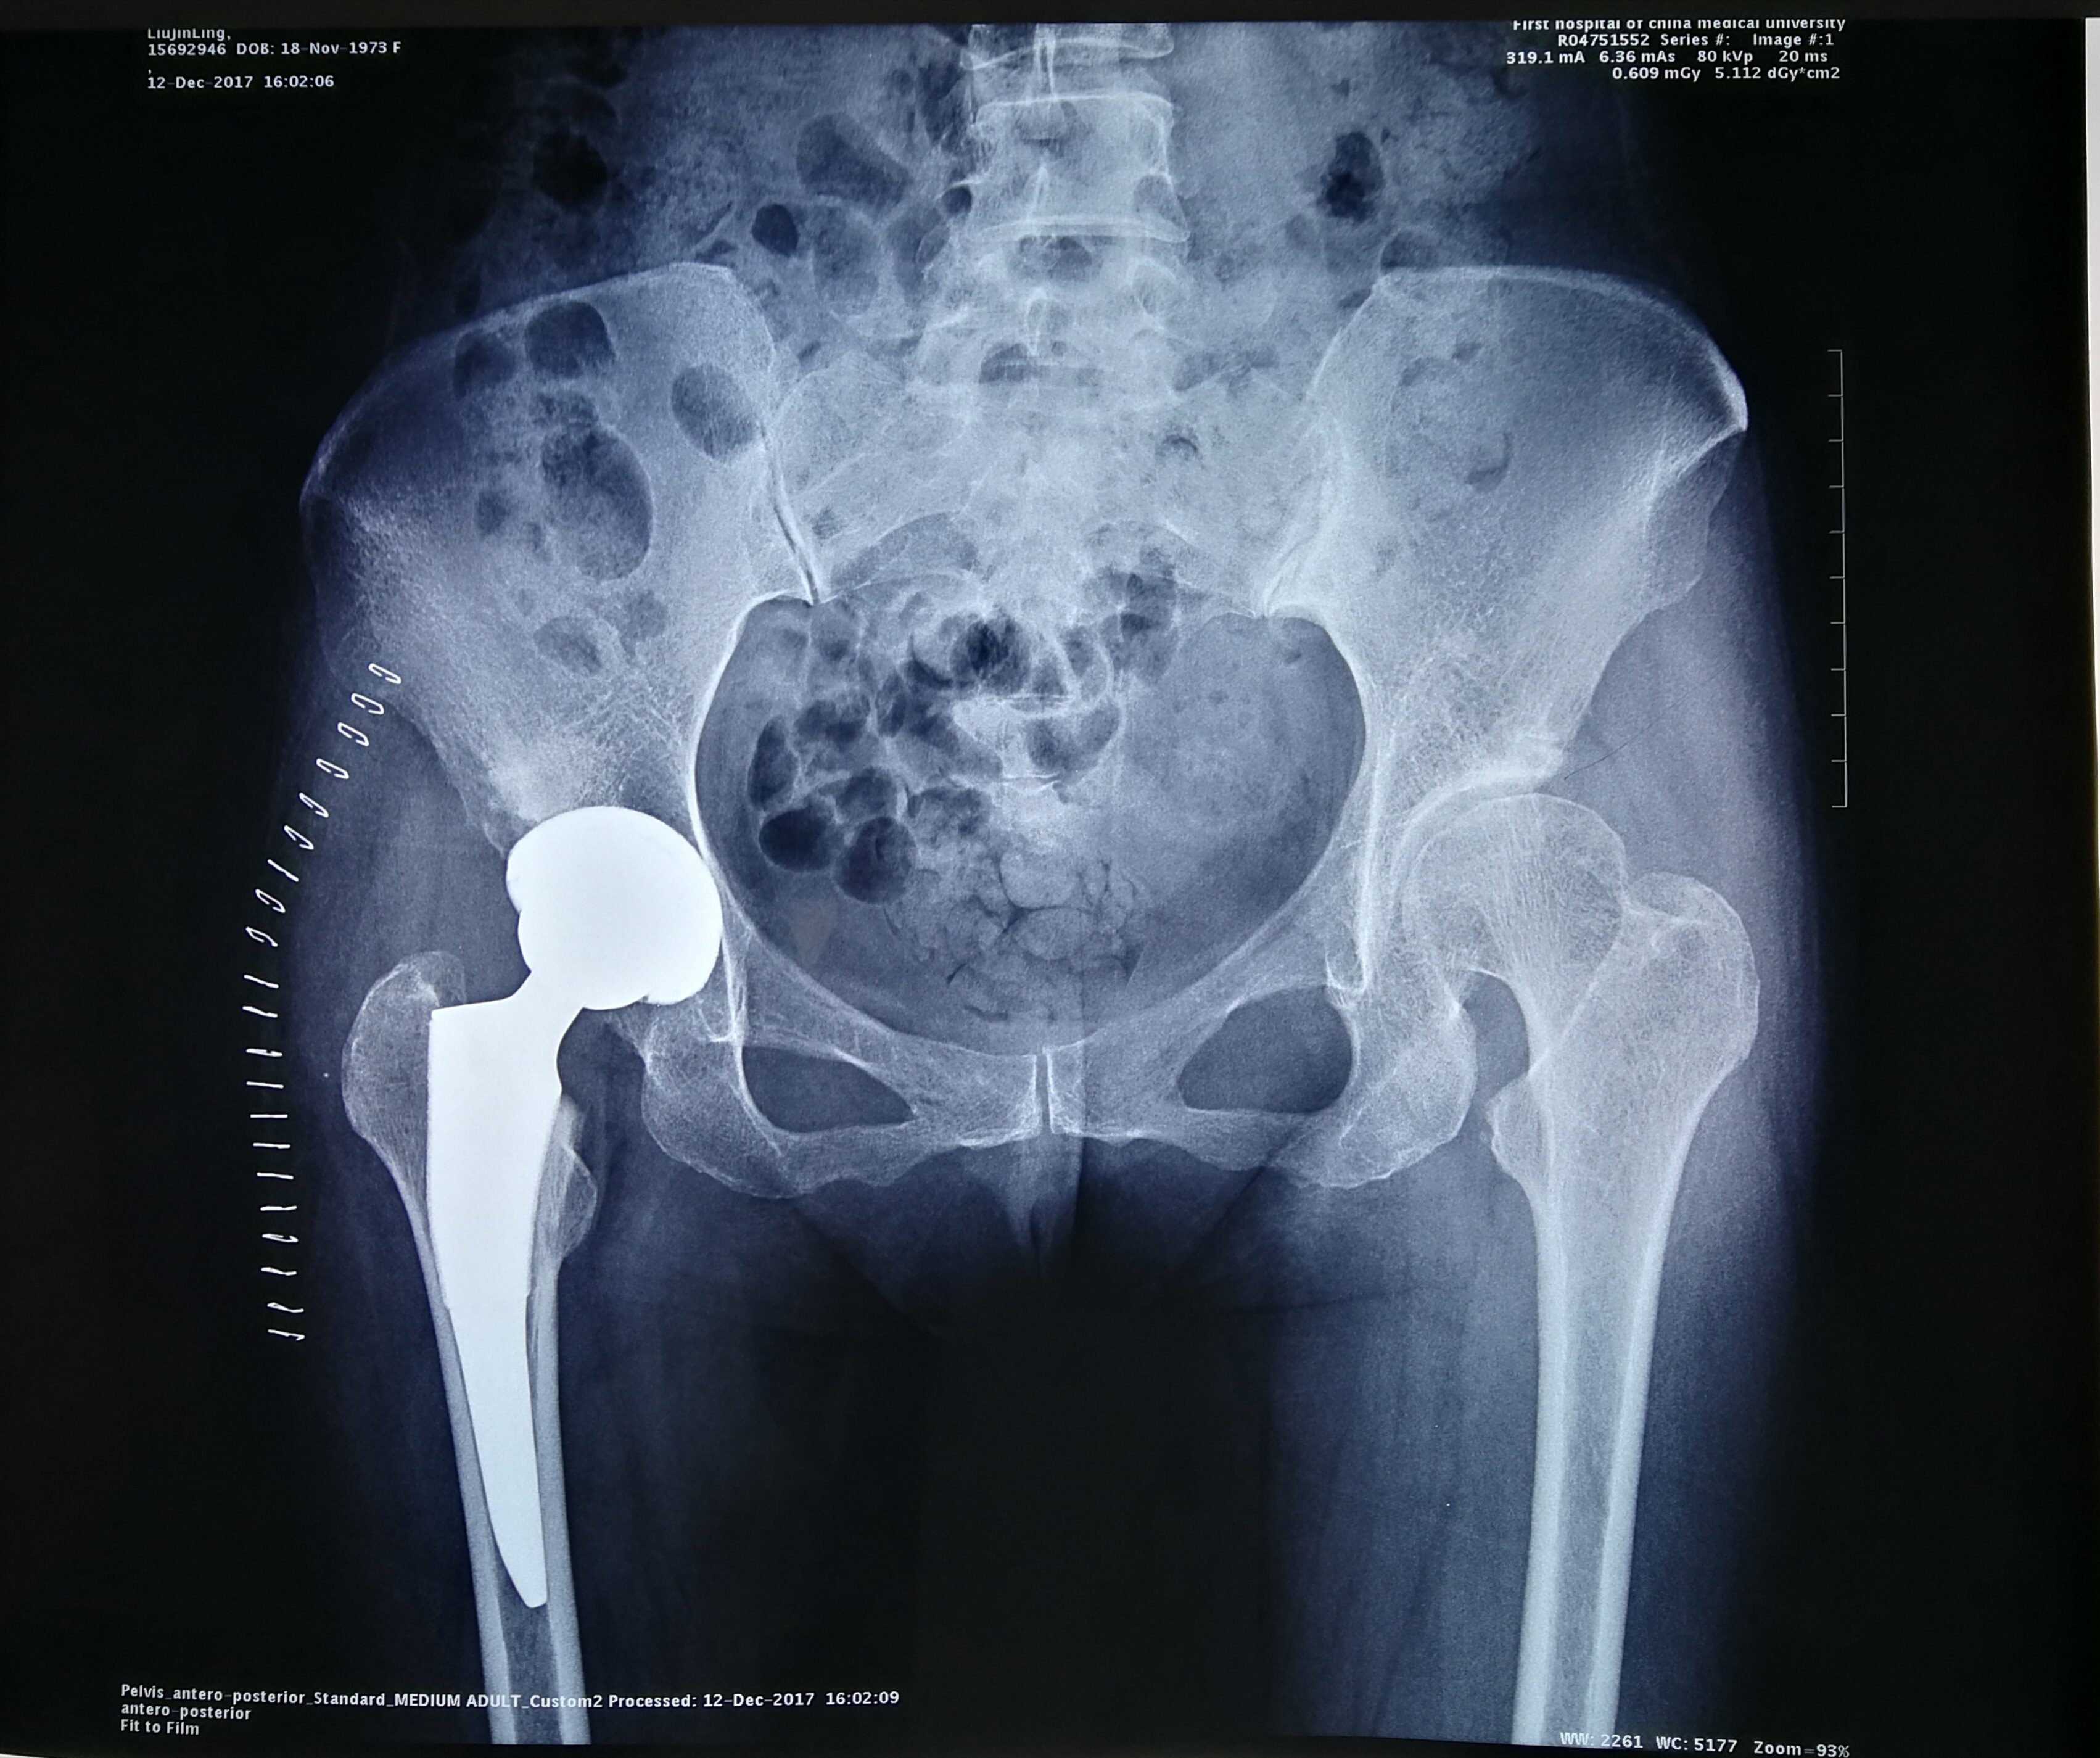

2012年10月15日 目的探讨全髋关节置换治疗成人发育性髋关节发育不良DDH的临床疗效方法2007年10月2010年12月擅长:成人发育性髋关节发育不良、DDH人工关节置换术、运动医学。号贩子挂号,效率第一,好评如潮,对我科16例发育性髋关节发育不良患者行全髋关节置擅长:成人发育性髋关节发育不良、DDH人工关节置换术、运动医学。号贩子挂号,效率第一,好评如潮;2017年12月24日 成人DDH的全髋关节置换技术_临床医学_医药卫生_专业资料 谢谢大家 !更多内容请进溜达网址导航 成人DDH的全髋关节置换技术谢谢大家。

2015年1月22日 人工全髋关节置换术已经成为治疗DDH晚期并发严重骨关节炎的患者的最佳选择擅长:成人发育性髋关节发育不良、DDH人工关节置换术、运动医学。号贩子挂号,效率第一,好评如潮,而由于 关节置换术的关键所在这种观点适合于绝大多数髋关节发育不良继。